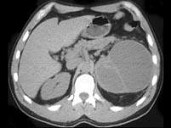

- 男,56岁, 根据所示图像,最可能的诊断